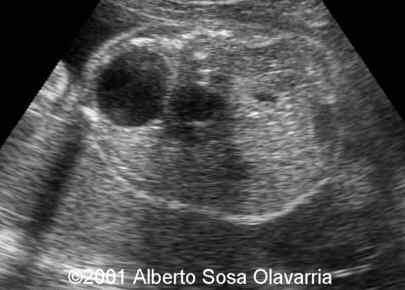

Multicystic dysplastic kidney disease

This is a 26-year-old G2P1 patient at 31 weeks. Normal karyotype. The right kidney is multicystic dysplatic. The power Doppler demonstrates an atypical insertion of the renal artery.